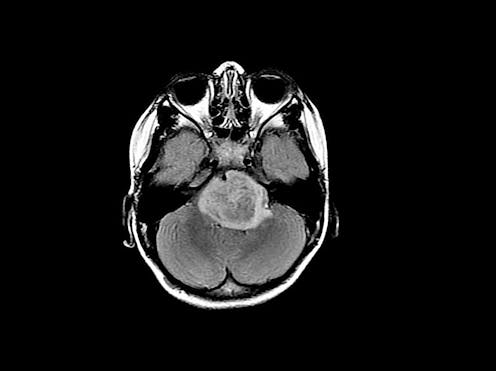

Our group has been developing new ways to identify disease in scans like MRI and CT, as well as digitized tissue slide images.

In another study involving MRI scans from prostate cancer patients, our computer algorithms identified clinically significant disease in more than 70 percent of cases where radiologists missed it. In half of the cases where radiologists mistakenly thought that the patient had aggressive prostate cancer, the machine was able to correctly identify that no clinically significant disease was present.